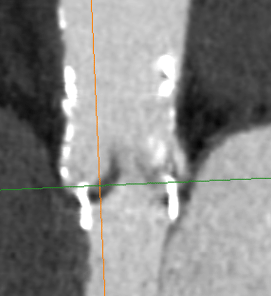

HALT

- HALT = Thrombus sur le feuillet

- RLM = Feuillet qui ne bouge pas bien en Systole/Diastole